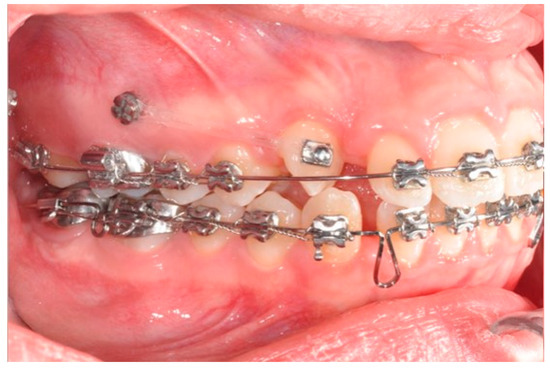

Figure 9. Canine and incisor distalization strategy: The cantilevers produce intrusion of the incisors and torque control during retraction.

2.3. Canine and Incisor Distalization

In this case, right after the spontaneous eruption, a power chain from the right tad was used to derotate and distalize the right upper canine (Figure 8). On the upper arch, a 0.20 × 0.25 SS wire was prepared with modified “cactus-shaped” closing loops, with the aim to close the space between the canines and the laterals. The cactus loop has a double aim. First of all, it is used as a closing loop; activation is produced by tying the loop through a metallic ligature from the tads. Secondly, it serves as a hook for cantilevers. The cantilevers are made using 0.19 × 0.25 TMA. The retraction of the upper incisors is supported by two cantilevers applied distally on the tads. The cantilevers will support the mechanics in order to produce intrusion of the incisors and torque control during retraction [1] (Figure 9 and Figure 10).